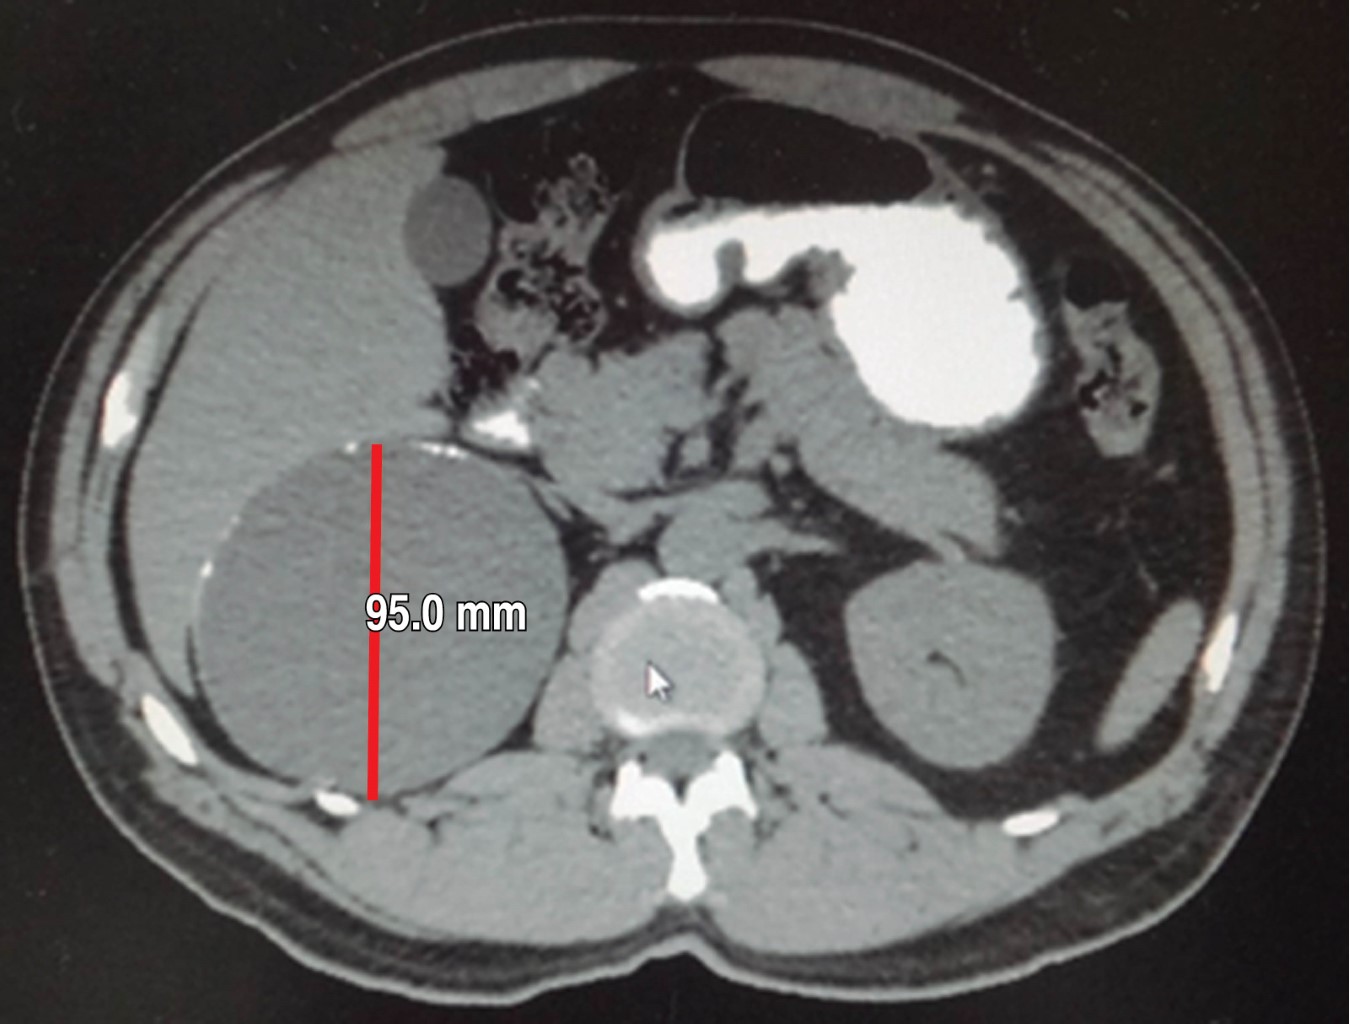

Biometría hemática, pruebas de función hepática, renales, TP y TPT de mayo de 2018 normales. No se realiza cortisol, aldosterona, catecolaminas urinarias ni metanefrinas. Tomografía de mayo reporta en glándula suprarrenal derecha imagen hipodensa con diámetros máximos de 101 mm, calcificaciones en su interior con efecto ocupativo y compresivo sobre las estructuras vecinas (Figuras 3, 4, 5 y 6). Completándose su valoración preoperatoria por medicina interna, se programa abordaje quirúrgico anterior abierto y bajo profilaxis antibiótica con ceftriaxona 2 g en dosis única, se realiza incisión subcostal derecha, destechamiento con electrocauterio de quiste suprarrenal derecho de 10 × 9 cm, con adherencias al hígado, contenido de aproximadamente 400 ml de líquido hialino y calcificaciones de alrededor de 20 × 40 mm en su interior. Se coloca drenaje abierto, penrose de ½" (19 mm) en espacio subfrénico ante la sospecha de hemorragia postoperatoria.

Figura 4

Figura 5